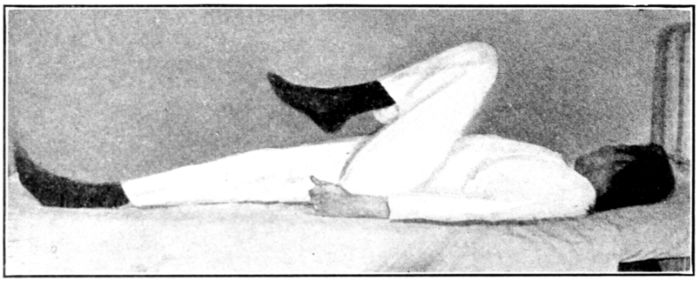

| 129, 130, 131, 132, 133, 134, 135. | Bed exercises taken during the puerperium | 350 to 353 |